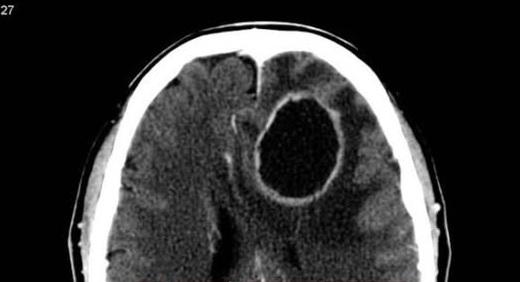

醫生公布老婦的檢查影像,顯示她患上腦部膿瘍。(互聯網)

泰國一名醫生警告,若不理會蛀牙,可能會受細菌感染而引發腦部膿瘍(brain abscess,腦部發生化膿性感染)。一名老婦因為四肢無力等症狀前去求醫,醫生初步懷疑是中風,但經過X光檢查,才發現她腦部有一處巨大的膿瘍,超因是她滿口蛀牙。

醫生指出,腦膿瘍是一種由細菌或真菌感染引發的嚴重病症,會導致腦部發炎化膿,在腦組織內形成潰瘍和膿液,可能會造成神經系統異常。若不及時治療而終致膿瘍破裂,恐會致命。